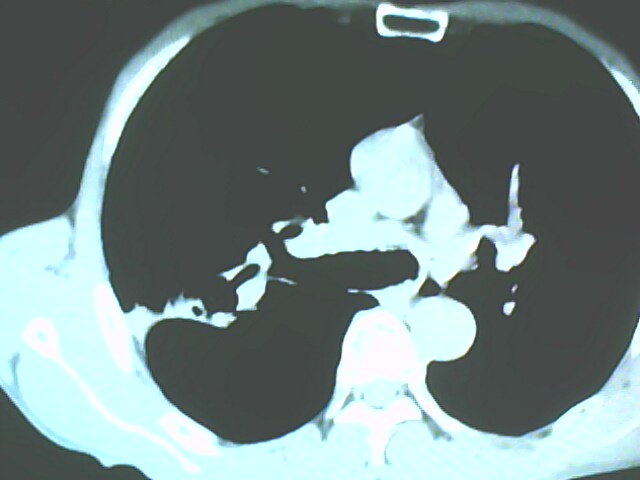

患者,男,66岁,以咳嗽、咳痰伴胸痛来就诊。

胸片提示右上肺占位病变。请各位老师看看ct。

从年龄及影像特征均支持癌性空洞。

考虑右肺上叶后段周围型肺癌并癌性空洞形成。

典型癌性空洞(偏心性,壁厚薄不均,内壁不光整),周围毛刺较僵硬,且有刺突征和血管聚集征